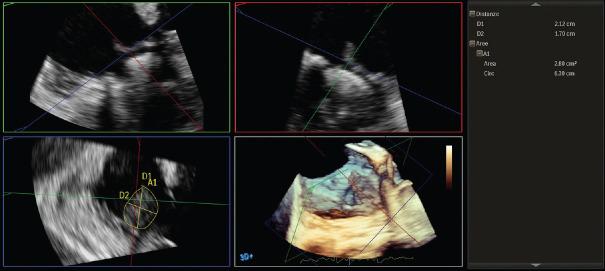

Infective endocarditis (IE) diagnosis is based on a clinical suspicion supported by consistent microbiological and instrumental data. Evidence of involvement of cardiac valves (native or prosthetic) or prosthetic intracardiac material is a major diagnostic criterion of IE. Transthoracic echocardiography (TTE) is the initial technique of choice for the diagnosis while transesophageal echocardiography (TEE) is recommended in patients with an inconclusive or negative TTE, in patients with high suspicion of IE, as well as in patients with a positive TTE, in order to document local complications. Repeating TTE and/or TEE should be considered during follow-up of uncomplicated IE, in order to detect new silent complications and monitor vegetation size. In the setting of IE, the role of three-dimensional (3D) TEE is increasing; in fact, this technique has also been shown to be useful for the diagnosis of IE and its complications as it allows to obtain infinite planes and volumetric reconstructions. In this review, we will describe the usefulness of 3D-TEE and its added value in the management of IE.

感染性心内膜炎(IE)的诊断基于临床怀疑,并辅以一致的微生物学和影像学数据。心脏瓣膜(天然或人工)或人工心内材料受累的证据是IE的主要诊断标准。经胸超声心动图(TTE)是诊断的首选初始技术,而对于TTE结果不确定或为阴性的患者、高度怀疑IE的患者以及TTE结果为阳性的患者,推荐行经食管超声心动图(TEE)检查,以记录局部并发症。对于无并发症的IE患者,在随访期间应考虑重复进行TTE和/或TEE检查,以便发现新的隐匿性并发症并监测赘生物大小。在IE的情况下,三维(3D)TEE的作用越来越大;事实上,该技术也已被证明对IE及其并发症的诊断有用,因为它可以获得无限平面和容积重建。在本综述中,我们将描述3D-TEE的实用性及其在IE管理中的附加价值。